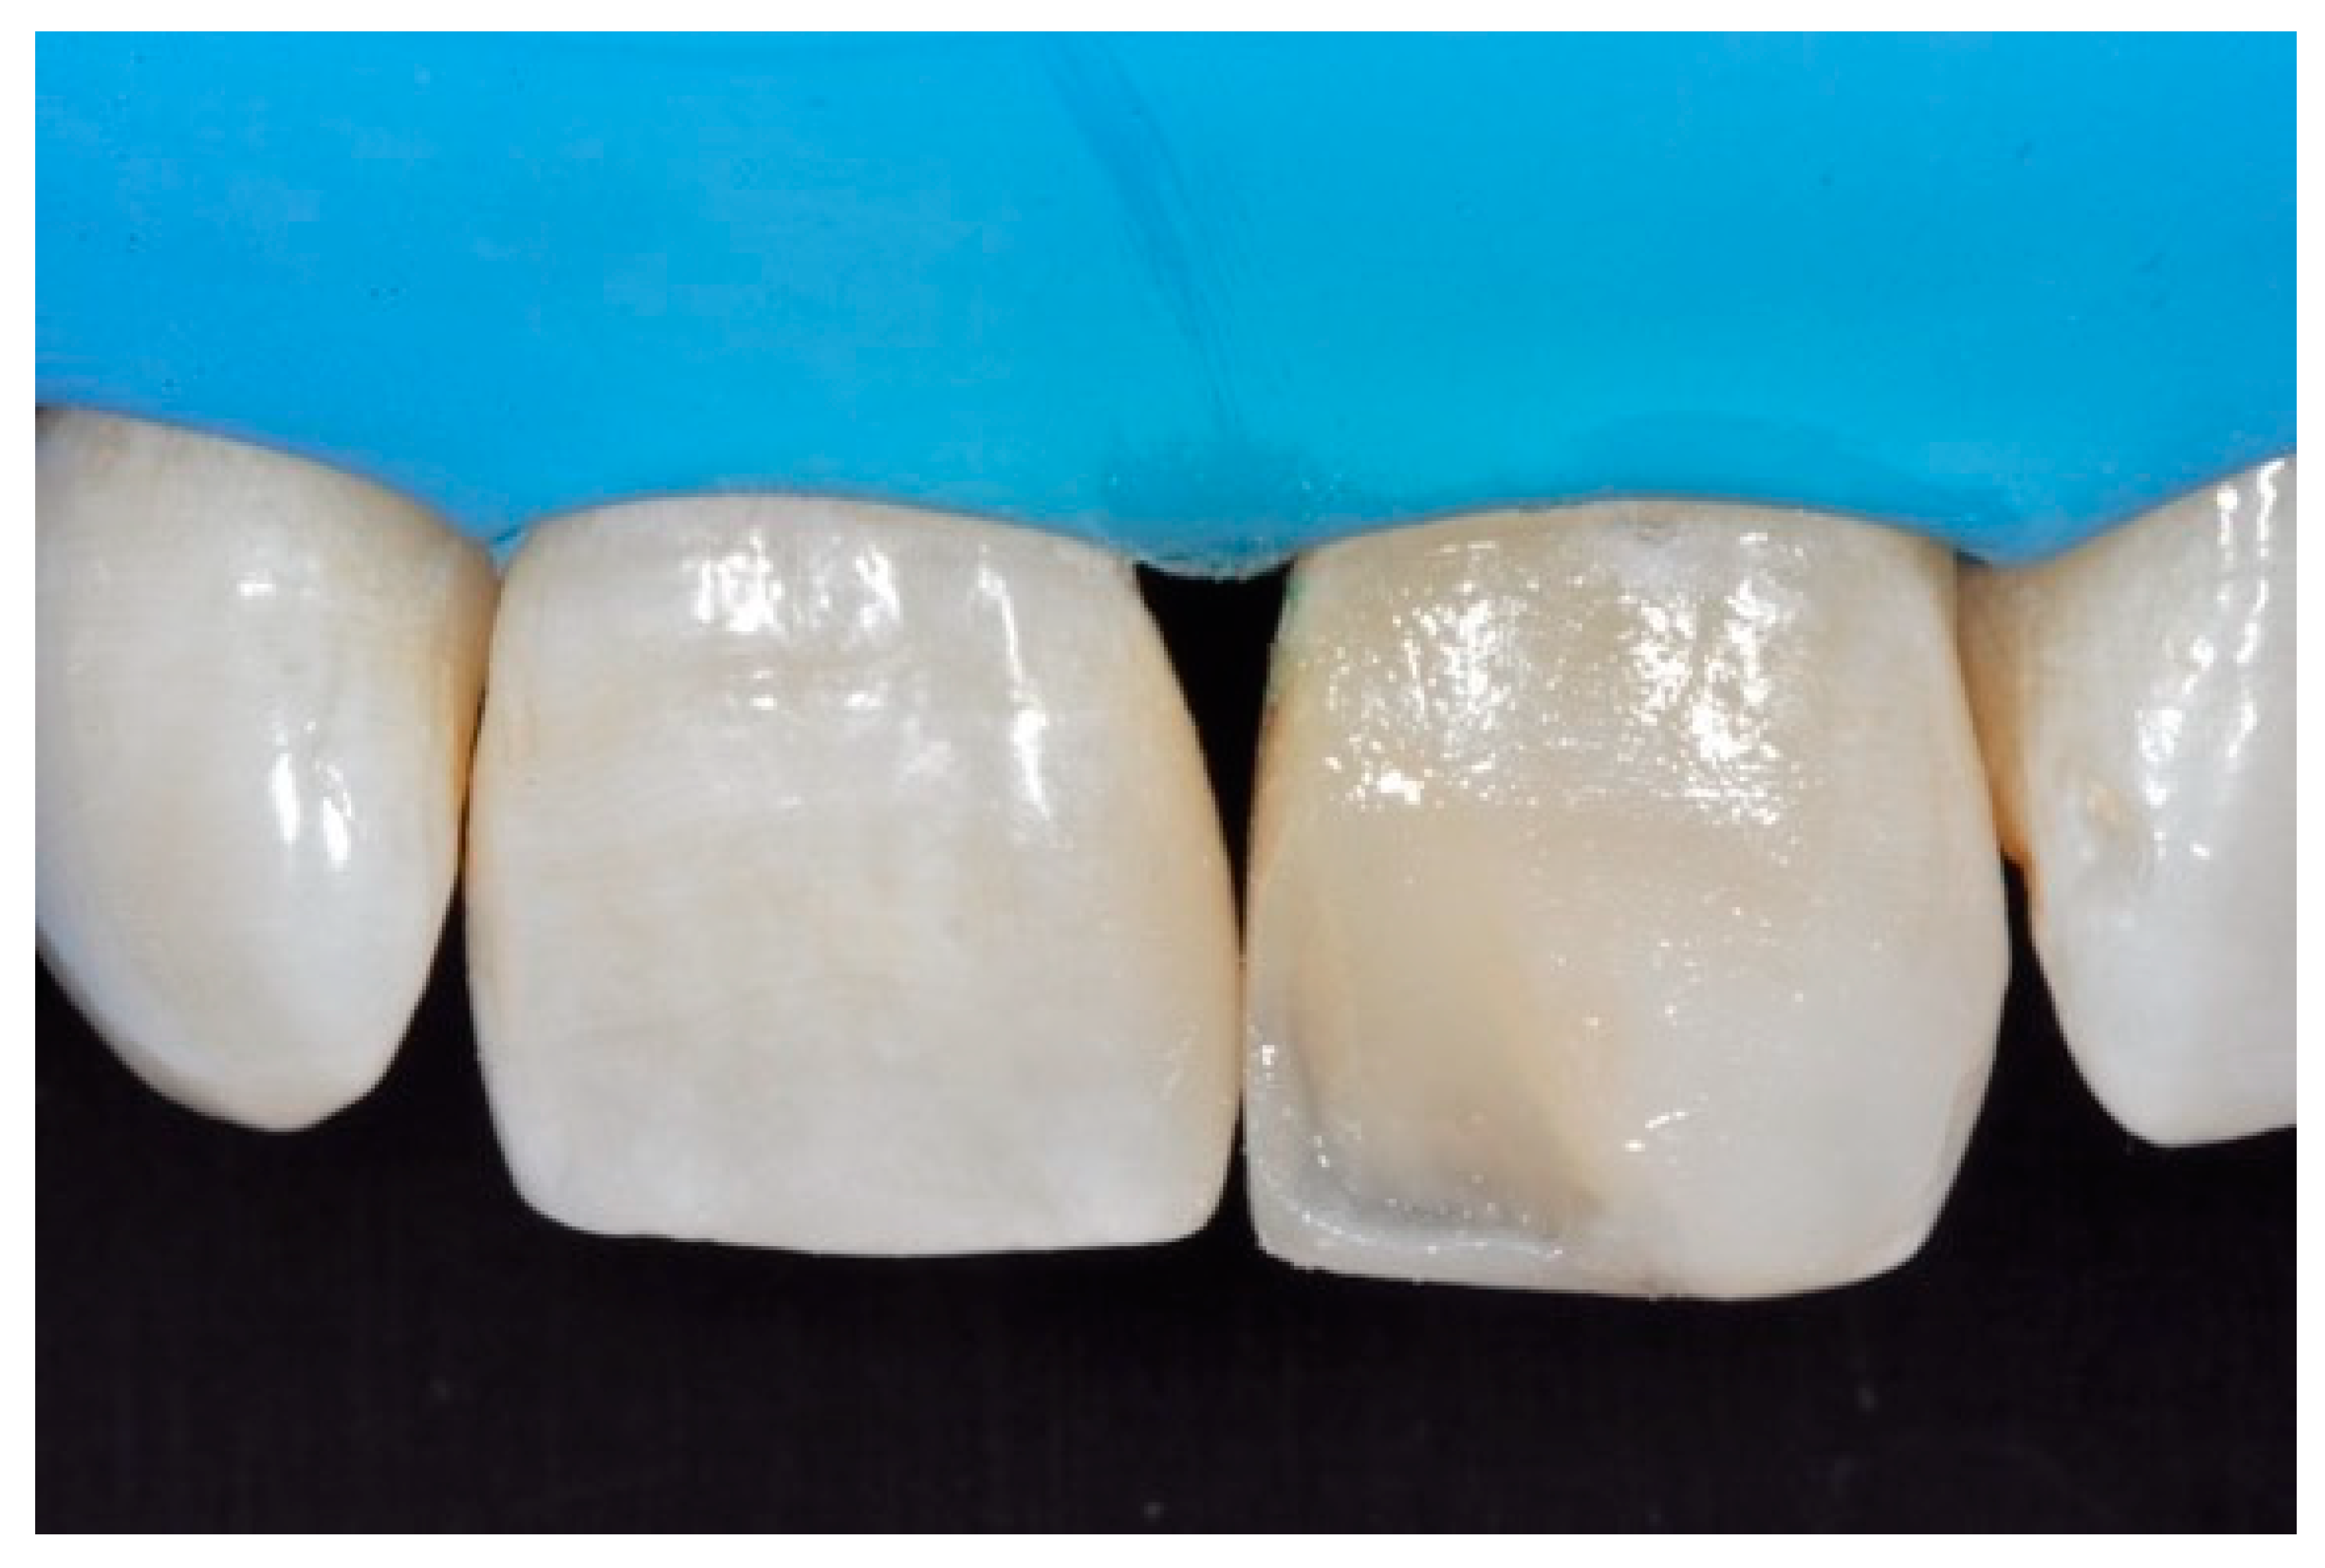

A 42-year old woman presented to the clinic with esthetic concerns related to her upper left lateral incisor (Figure 20). Pre-operative x-rays showed periapical lesion that required retreatment. After retreatment (Figure 21) a treatment plan was proposed to the patient. The ideal treatment would have involved an orthodontic therapy to gain back lost space in mesial portion. The patient decided not to consider an orthodontic treatment and accepted just the restorative proposal (Class IV restoration). Considered the sufficient amount of ferrule no post was applied [16]. Shade was selected as described in previous case, using the button-try technique [14]. After isolation with rubber dam, preparation (Figure 22) and adhesion (Clearfil SE, Kuraray Noritake Dental, Tokyo, Japan), composite frame was completed (Clearfil Majesty ES-2, A1D, Kuraray Noritake Dental, Tokyo, Japan) with silicone index and interproximal transparent mylar matrices (Figure 23). Interproximal walls were considered too thick; therefore, they were reduced (Figure 24) using diamond bur as described in Section 2.1.2. This allowed the internal dentinal body to have the correct volume (Figure 25) and therefore to respect ideal opacity/translucency ratios. Restoration was therefore completed adding enamel layer (Clearfil Majesty ES-2, A1E, Kuraray Noritake Dental, Tokyo, Japan) and performing finishing and polishing procedures (Figure 26 and Figure 27) as described in previous clinical case. The restoration shows good integration 6 months post-operative (Figure 28 and Figure 29).

Figure 25.

Internal dentinal anatomy. Reprinted from Restauri diretti nei settori anteriori, G. Paolone, S. Scolavino, © 2021, with permission from Quintessence Publishing Italy.